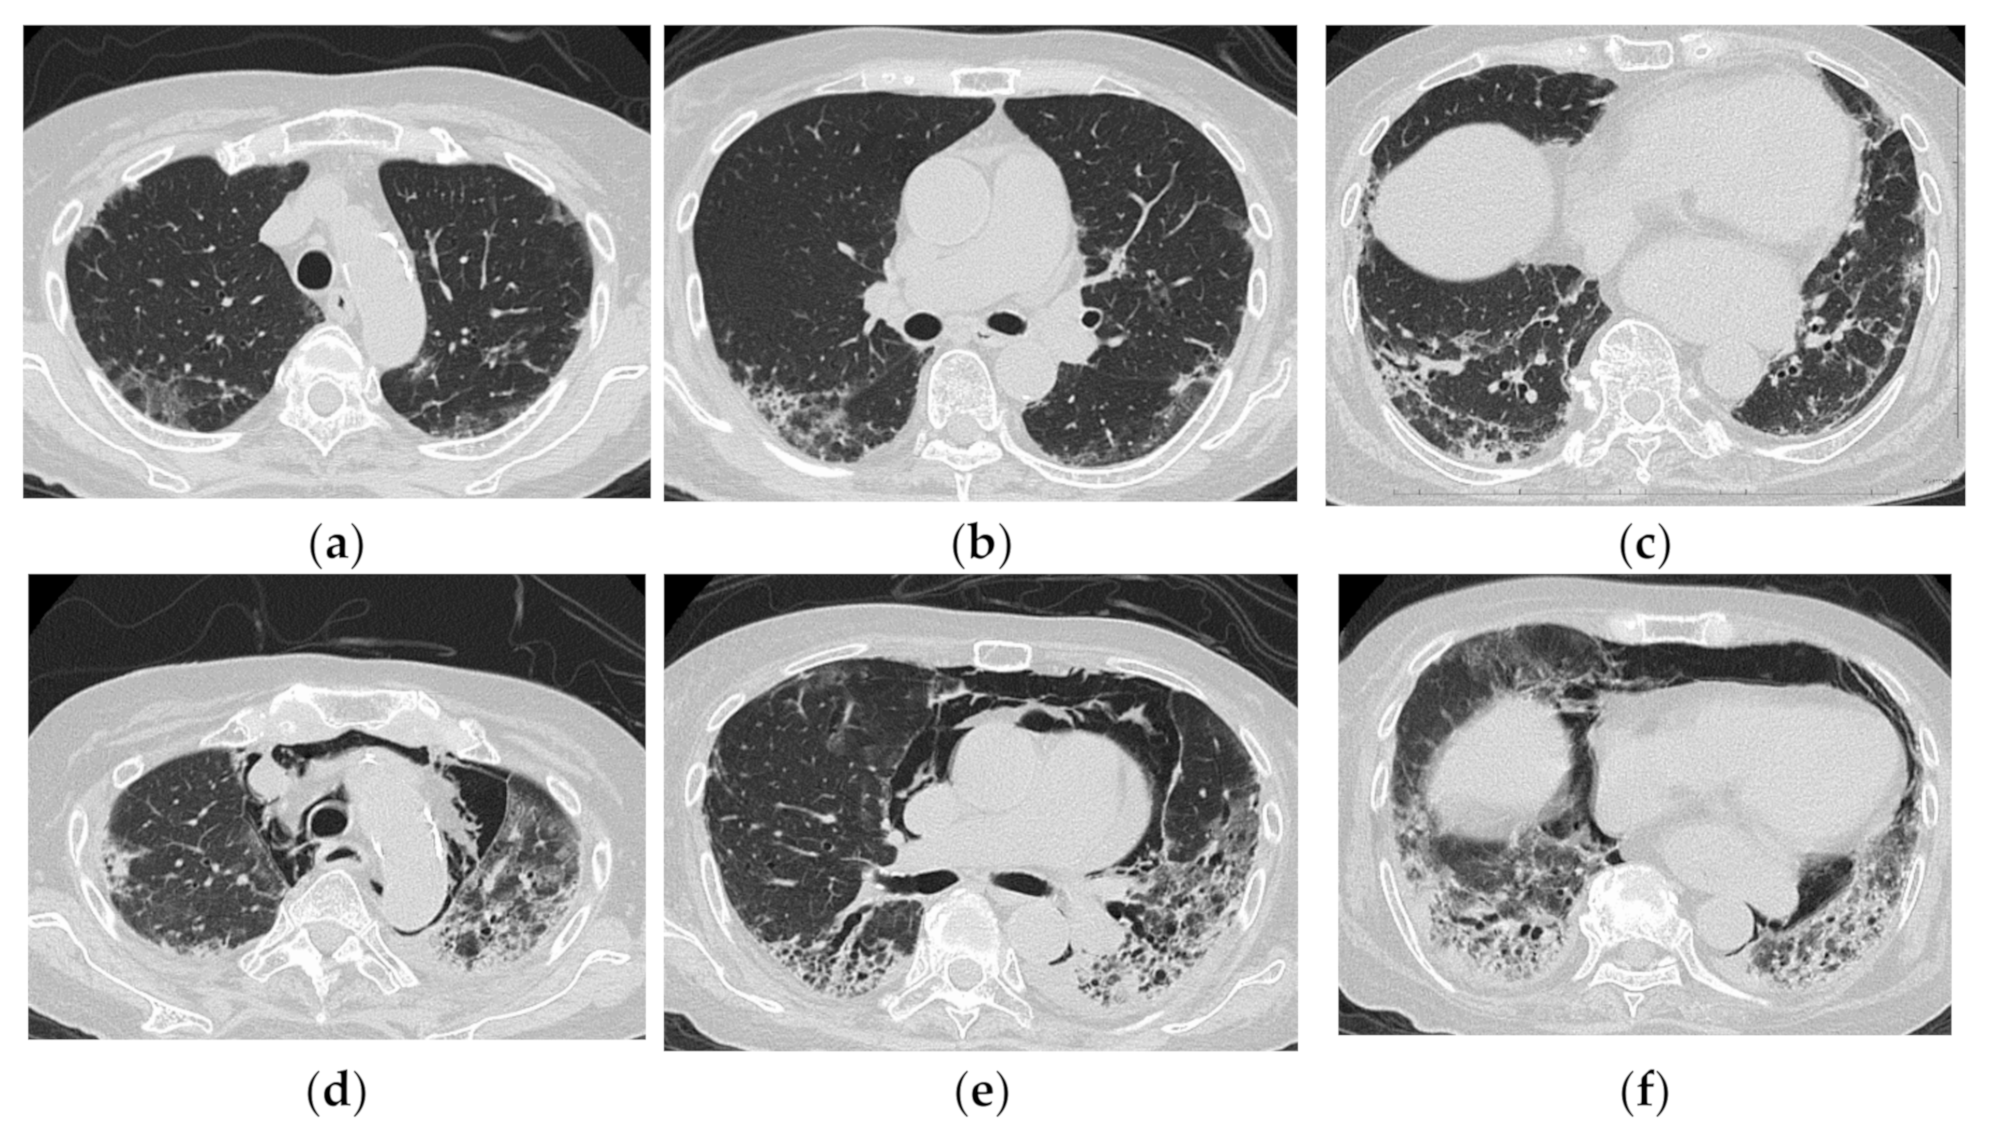

2.2. Acute Type

4. HRCT Findings in Relation to the Poorer Prognosis

5. Clinical Pearls from HRCT Findings